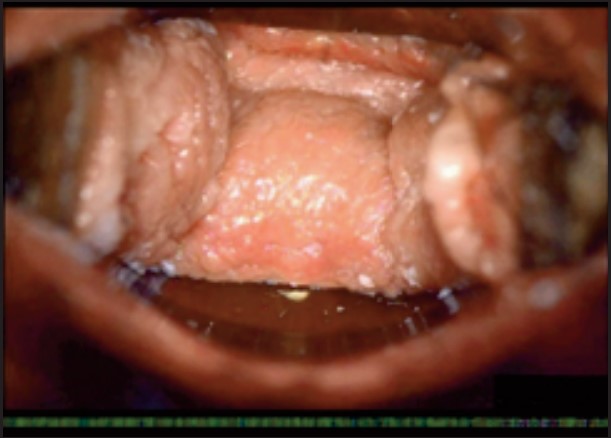

У пацієнток 1, 2 і 3 вагінальні складки утворилися та увиразнилися помітніше та сильніше, ніж вони були до лікування, ми оцінили цей клінічний результат після 1-го сеансу (через 16 діб). На нашу думку, такі виразні складки свідчать про підтяжку слизової оболонки піхви, що добре впливає на ущільнення піхви та проблему нетримання сечі. Через 36 діб після процедури ми спостерігали, що зруйнована анатомічна структура піхви відновила Н-подібну форму, тобто стала набагато здоровішою. Зокрема, у пацієнтки 4 структура піхви була цілковито зруйнована, стінки піхви обвисали через втрату еластичності. Однак через 36 днів після процедури структура піхви повністю відновила здорову Н-подібну форму [Див. Малюнок 3].

Пацієнтка №4

До

Після 36 діб

| Вік | 51 |

| Пологи | Природні. 2 хлопчики. |

| Лікування | 2 сеанси / 1 місяць |

| Огляд | 36 діб |

| Протокол | 1 сеанс – 440 імпульсів 2 сеанс – 200 імпульсів |

| Результати | √ Істотне відновлення H-подібної структури √ Зменшилася секреція √ Підтяжка |